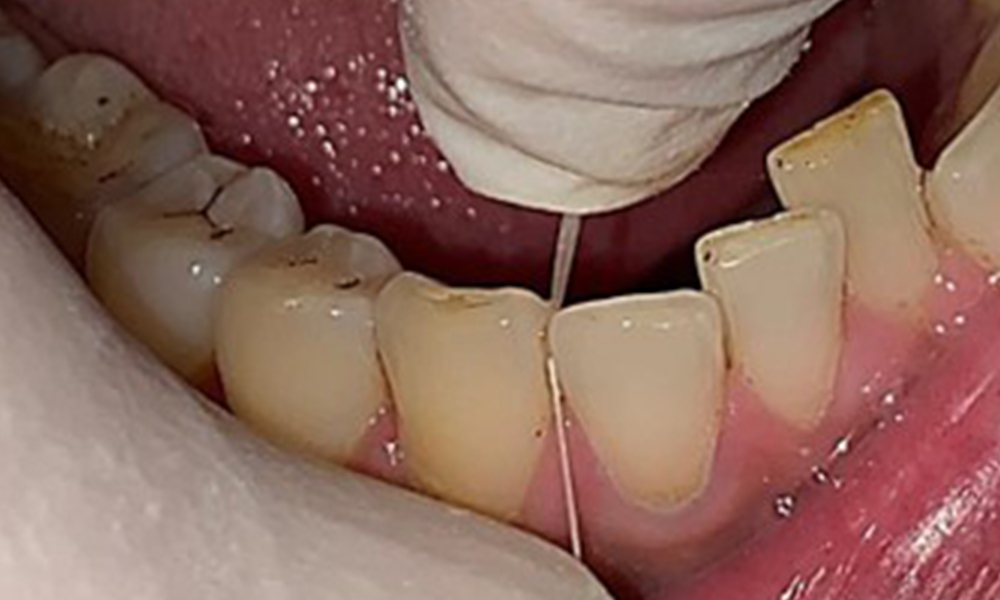

Instruction and motivation are important components of these appointments. Good home-based intraoral hygiene behaviour and understanding are important for patients. Plaque accumulation is particularly evident in the cervical regions (Fig. 8).

These must be discussed with the patient, and improvements to the teeth-brushing technique must be practised. A soft toothbrush attachment is recommended for home-based intraoral hygiene due to the presence of erosions and attritions.